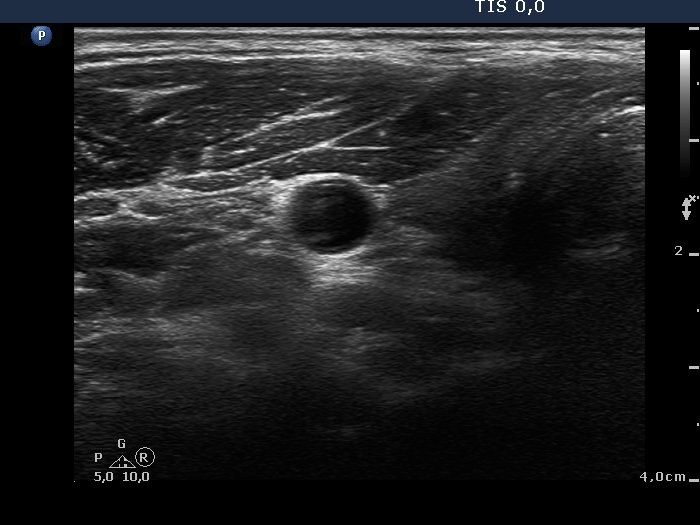

First examination (1st to 3rd rows of images):

Ultrasonography: Both lobes presented hypoechogenic ill-defined areas. The echogenicity index was 80% in the right lobe while 20% in the left thyroid. The vascularization was significantly decreased.

Elastography demonstrated hard areas according to the hypoechogenic field in the left lobe while almost the entire right lobe proved to be hard.Cytological diagnosis: subacute, granulomatous de Quervain's thyroiditis.